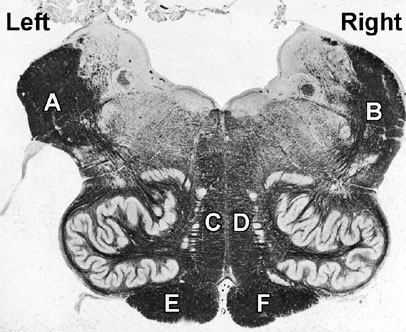

A 57-year-old man is brought to the emergency department 1 hour after he suddenly collapsed at home. He regained consciousness 5 minutes later. He has a 5-year history of hypertension. Neurologic examination shows dysmetria on the right. Sensation to pain and temperature is decreased over the right side of the face. Which of the following labeled regions in the photograph of the myelin-stained cross section of the brain stem shown is most likely damaged in this patient?